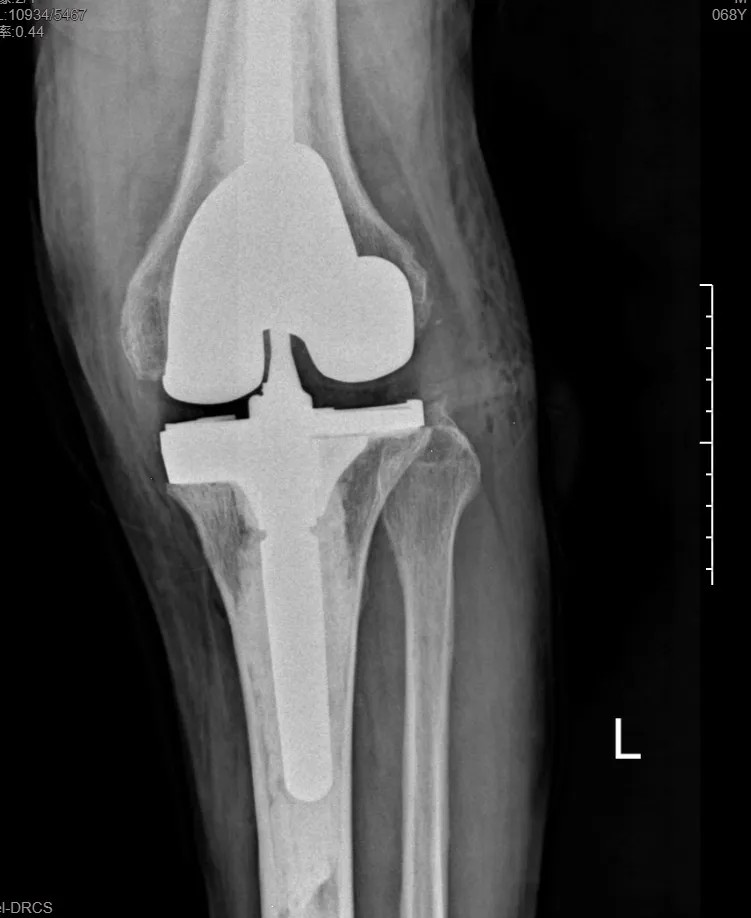

本次手術(shù)的核心,是采用了Evolution® ECCK膝關(guān)節(jié)翻修系統(tǒng)。該系統(tǒng)專為應(yīng)對(duì)翻修手術(shù)中常見(jiàn)的嚴(yán)重骨缺損、韌帶功能不全等極端復(fù)雜情況而設(shè)計(jì)。

其模塊化的組件提供了前所未有的靈活性,就像一套高精度的“工程套件”,允許醫(yī)生在術(shù)中根據(jù)實(shí)際骨缺損情況,自由組合不同尺寸的墊塊、延長(zhǎng)桿等部件,實(shí)現(xiàn)關(guān)節(jié)線和力學(xué)穩(wěn)定性的個(gè)體化重建。

尤為重要的是,該系統(tǒng)保留了內(nèi)軸型假體的設(shè)計(jì)哲學(xué),在重建關(guān)節(jié)穩(wěn)定性的同時(shí),努力模仿了人體膝關(guān)節(jié)自然的運(yùn)動(dòng)方式(內(nèi)軸穩(wěn)定性、外側(cè)活動(dòng)性),旨在讓患者術(shù)后不僅能走,還能走得更舒適、更自然。

集多項(xiàng)前沿科技于一體的精準(zhǔn)手術(shù),帶來(lái)了令人欣喜的結(jié)果。術(shù)后第一天,在醫(yī)生指導(dǎo)下,張先生便能夠借助助行器下地站立、邁步行走。

“感覺(jué)非常好!膝蓋那里終于不痛了,而且自己能控制它了。”張先生的喜悅之情溢于言表。快速的功能恢復(fù),極大地增強(qiáng)了他的康復(fù)信心。